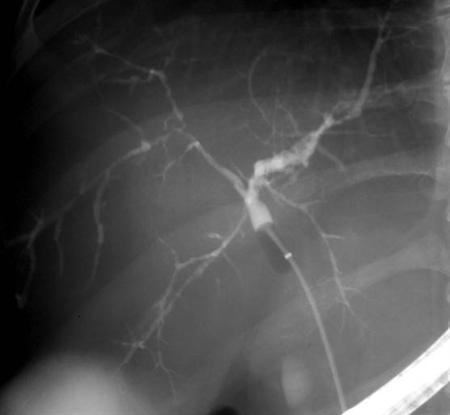

Xολαγγειοπαγκρεατογραφία σε ασθενή με πρωτοπαθή σκληρυντική χολαγγειίτιδαXολαγγειοπαγκρεατογραφία σε ασθενή με πρωτοπαθή σκληρυντική χολαγγειίτιδα Η φλεγμονώδης νόσος του εντέρου συνήθως, προηγείται της πρωτοπαθούς σκληρυντικής χολαγγειίτιδας, αν και σε μερικές περιπτώσεις η κολίτιδα είναι ασυμπτωματική και ανακαλύπτεται μετά από βιοψία.

Η διάγνωση της νόσου γίνεται με την βοήθεια της ERCP (ενδοσκοπική ανάστροφη χολαγγειοπαγκρεατογραφία) ή με MRCP, στην οποία αναδεικνύονται πολυεστιακές διάχυτες στενώσεις με ενδιάμεσα φυσιολογικά ή διατεταμένα τμήματα χολικών πόρων που τους προσδίδουν την χαρακτηριστική κομβολογιοειδή εμφάνιση.